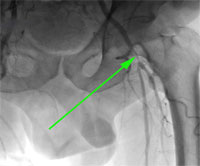

Рис.2. Дооперационная ангиография. Стеноз левой поверхностной бедренной артерии в среднем сегменте до 80%.